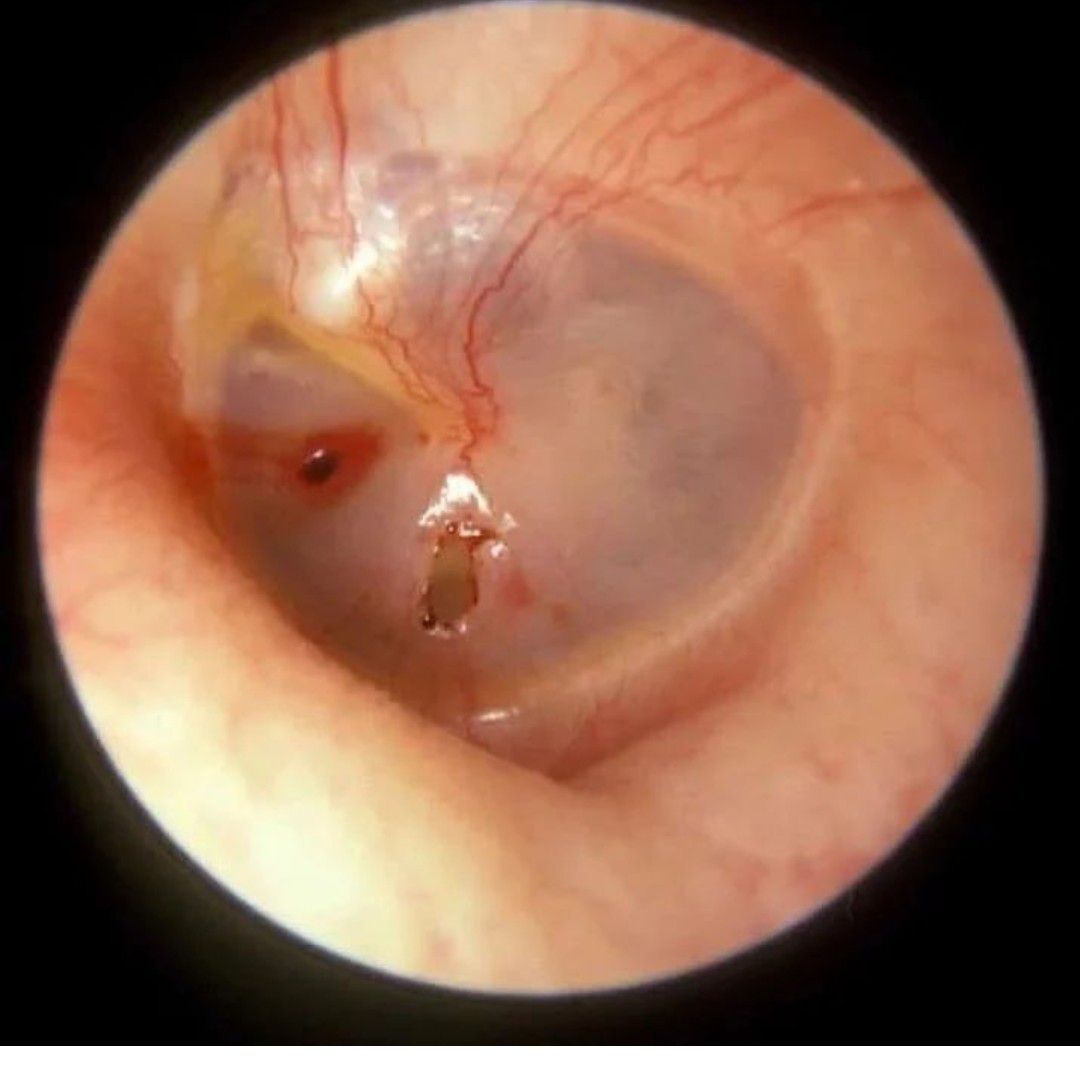

A patient came with the history of ear pain and hearing loss. What might be the diagnosis?

Diagnosis

ENT

Ear

Membrane

Tympanic